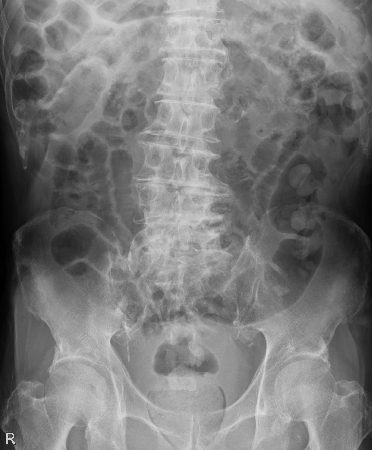

症例は 80代の男性患者さんで、脳梗塞後遺症で急性期病院から転院してきた方です。

前医から経鼻胃管からの経管栄養を投与しており、小生が担当した時には

既に長期に渡って臥床が続いていました。

ご本人とご家族の強いご意向で、胃瘻造設は行わず、経鼻胃管での栄養投与を継続していました。

当時(この日を1日目とする)の腹部レントゲンを示します

(ちなみにこのレントゲンは、レントゲン、見方の味方5のレントゲンと同じものです)。

大腸ガス・小腸ガスが多く、腸管の動き(蠕動:ぜんどう)は かなり良くないようですね。

この時点では幸いにも嘔気や嘔吐、腹部の症状はなく、下剤のセンノシド 24mgを内服しており、

便通は1日に2回程度、軟便~泥状便が続いていました。